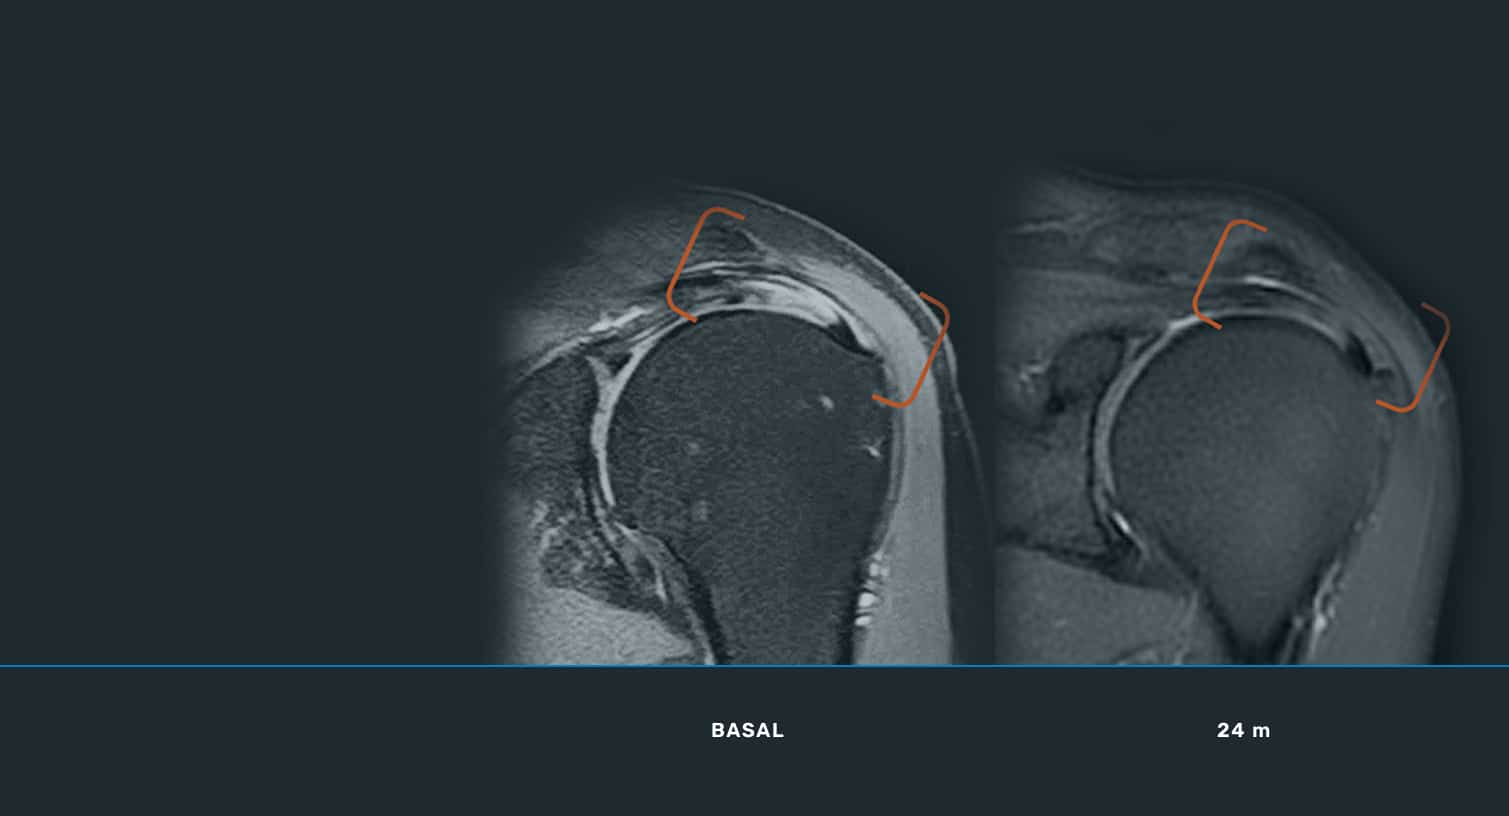

En ITRT hemos demostrado la viabilidad y seguridad de nuestras terapias mediante ensayos clínicos regulados y autorizados por la AEMPS (Agencia Española de Medicamentos y Productos Sanitarios). Una vez superado el ensayo clínico, la AEMPS autoriza el uso del medicamento en pacientes concretos, lo que permite ofrecer tratamientos personalizados con eficacia clínica y capacidad regenerativa demostrada.